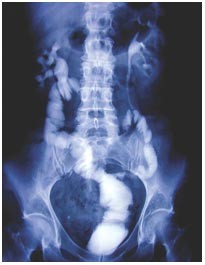

Investigations Intravenous urography and ureteroscopy.

Diagnosis Panurothelial superficial transitional-cell carcinoma.